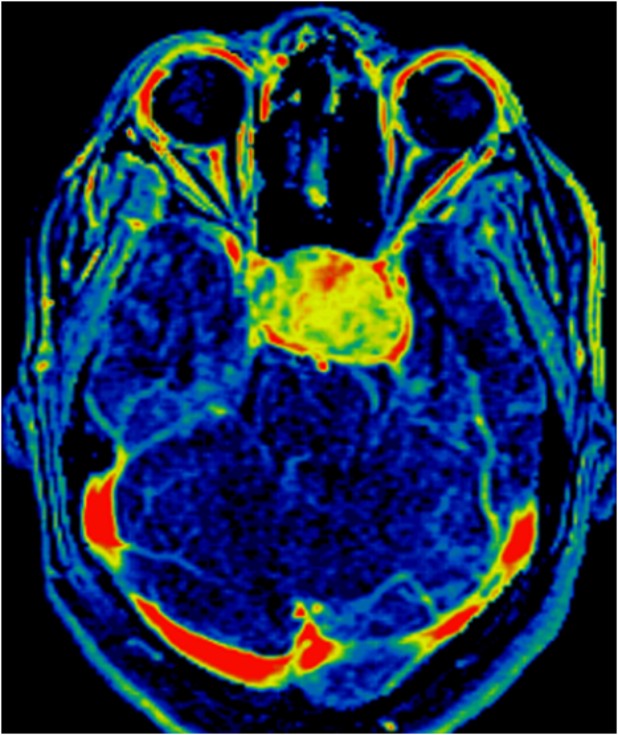

La radioterapia fa parte del trattamento del cancro e consiste nel controllare o uccidere le cellule maligne. Benché indolore, essa provoca effetti collaterali che vanno dalla stanchezza e l’irritazione della pelle, alla nausea, ai danni alle superfici epiteliali. Per i bambini sottoposti a questo trattamento, la radioterapia al cervello aumenta il rischio di soffrire degli effetti collaterali neurocognitivi permanenti, perché la radiazione coinvolge anche i tessuti sani. Di conseguenza, si formano meno nuove cellule, in particolare nell’ippocampo, un componente chiave del cervello che svolge un ruolo importante nella memoria e nell’orientamento spaziale.

Per questo studio, i ricercatori hanno valutato i pazienti pediatrici che sono stati trattati con radioterapia convenzionale per il medulloblastoma, una forma di tumore al cervello che colpisce soprattutto i bambini. Hanno anche fondato il loro studio su schemi di trattamento simulati utilizzando tecniche di terapia protonica e più recenti tecniche di terapia fotonica.

I risultati di questi schemi di trattamento hanno indicato che l’uso delle nuove tecniche di radioterapia mitigano il rischio di effetti collaterali neurocognitivi, in particolare la terapia protonica.

Secondo i ricercatori, la radiazione a raggi X e i raggi di elettroni tradizionali passano attraverso il corpo, aumentando così le probabilità di colpire il tessuto sano. L’energia di un fascio di protoni può essere variata in modo che raggiunga una determinata profondità. A differenza dell’irradiazione fotonica, i protoni possono essere concentrati sul tumore stesso, rendendo più difficile il danneggiamento dei tessuti sani e contribuendo a ridurre il rischio di effetti collaterali.